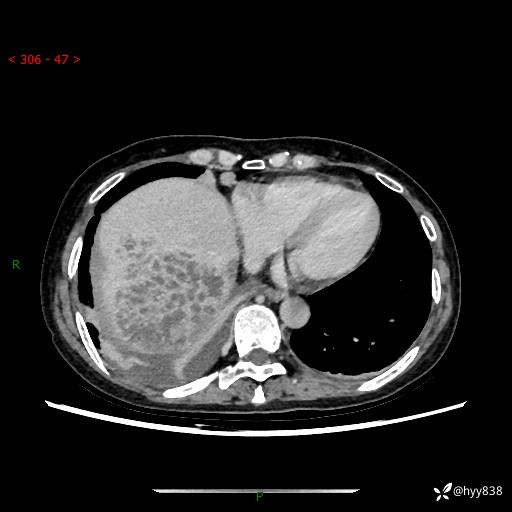

病例老年女性,发热来诊。如此“蜂窝煤”,治疗很棘手---结果公布~

性别:女

年龄:53岁

简要病史:发热(门诊急诊患者)

上腹部CT平扫